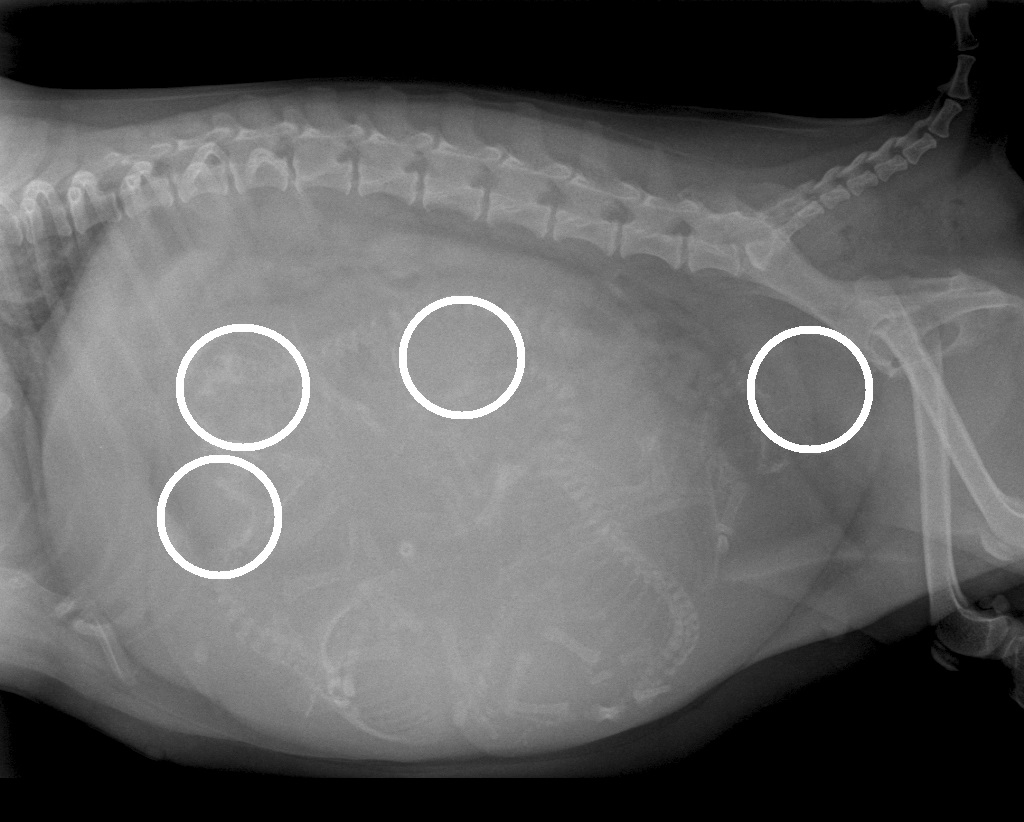

Rรถntgenfoto van Luna's buik: zoek de vier kopjes

De vier kopjes zijn wit omcirkeld

De meest rechtse ligt klem voor de bekkeningang van Luna